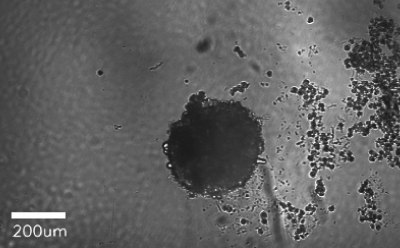

Figure 3.Representative microscopy images of Kupffer cell in culture after 48 hours.